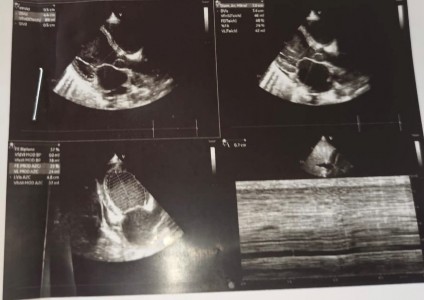

The echocardiogram evidenced left ventricular systolic dysfunction, with a left ventricular ejection fraction (LVEF) of 39 %, D-dimer 6.98 ug/mL, ferritin 522 ng/mL, TB 1.72, GOT 49, GPT 30, creatinine (Cr) 0.47 and CPK MB 12.20. Therefore, the prescribed treatment was captopril 6.25 mg po every 12 hours and carvedilol 3.125 mg po every 12 hours, and he continued his treatment with diuretics. Finally, he was discharged afebrile, without edema and with resolution of liver failure and coagulation disorder (Figures 2 and Figure 3).

Figure 3 Echocardiogram showing a spherical image of ventricular cavities with global hypokinesia, leading to left ventricle systolic dysfunction. Flows of mitral and pulmonary regurgitation can be observed.